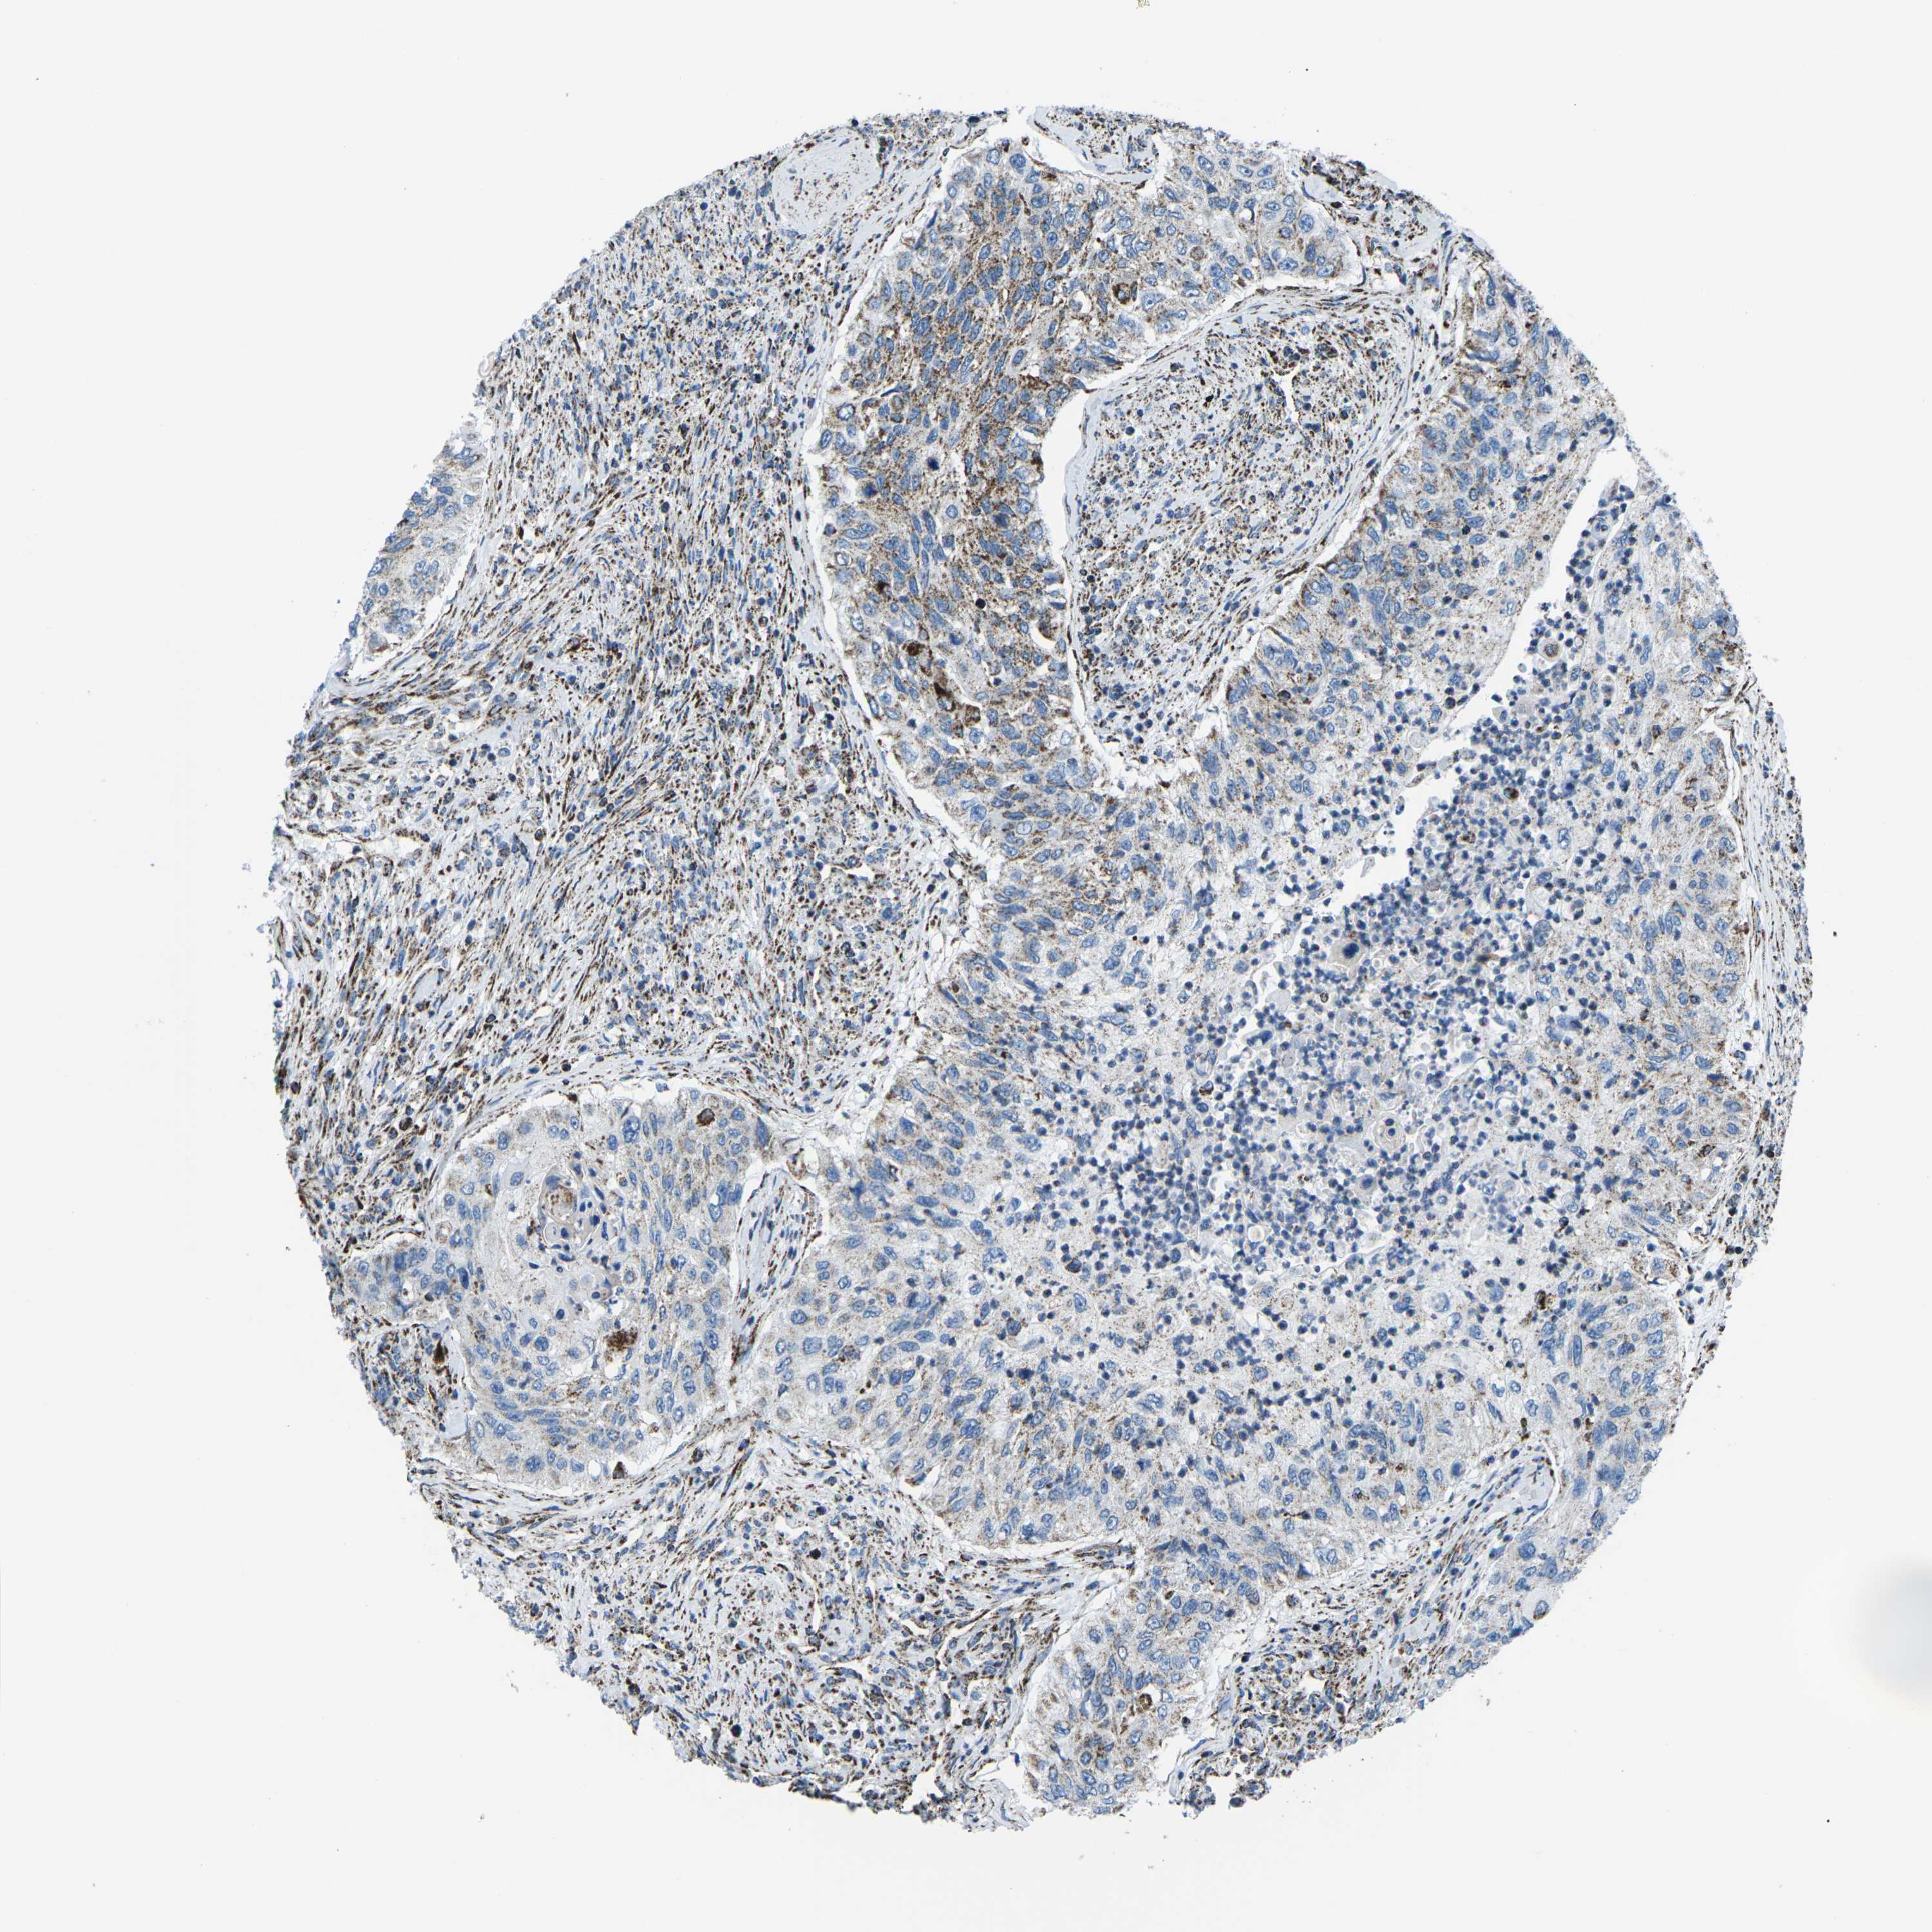

UROTHELIAL CANCER - Protein expressioni

A mouse-over function shows sample information and annotation data. Click on an image to view it in a full screen mode. Samples can be filtered based on level of antibody staining by selecting one or several of the following categories: high, medium, low and not detected. The assay and annotation is described here.

Note that samples used for immunohistochemistry by the Human Protein Atlas do not correspond to samples in the TCGA dataset.

Antibody stainingi

Antibody staining in the annotated cell types in the current human tissue is reported as not detected, low, medium, or high, based on conventional immunohistochemistry profiling in selected tissues. This score is based on the combination of the staining intensity and fraction of stained cells.

Each image is clickable and will lead to virtual microscopy that enables deeper exploration of all samples and also displays staining intensity scores, fraction scores and subcellular localization as well as patient and tissue information for each sample.

Antibody HPA051505

Antibody HPA054758

Antibody CAB016243

Staining

High

Medium

Low

Not detected

Intensity

Strong

Moderate

Weak

Negative

Quantity

>75%

75%-25%

<25%

None

Location

Nuclear

Cytoplasmic/membranous

Cytoplasmic/membranous,nuclear

Urothelial carcinoma, High grade

Urothelial carcinoma, Low grade